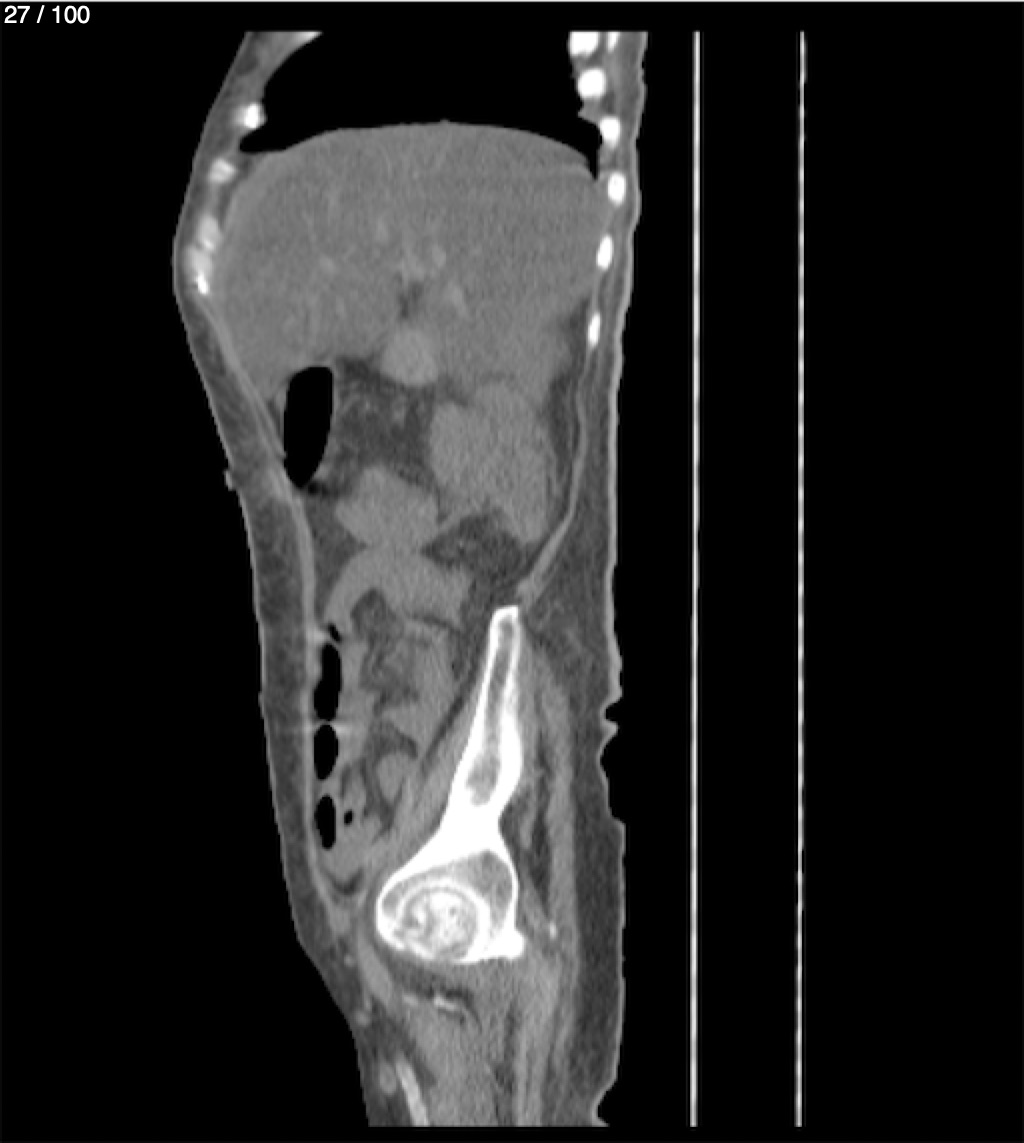

Hilda Geronimo Mendez 60A - T.C Abdomen Simple